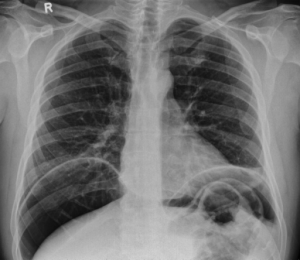

Free air under diaphragm (a complication of perforated ulcer).

• Consider acute abdominal series if concern for perforation (>50 years old; concerning abdominal exam)